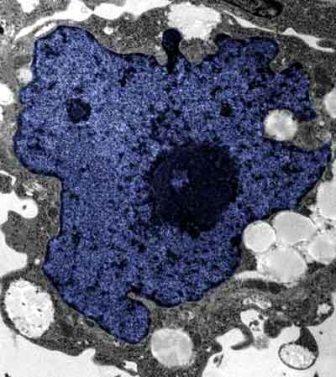

在成人體內(nèi)及胚胎內(nèi)發(fā)現(xiàn)的干細(xì)胞屬于主細(xì)胞,能發(fā)育成各種各樣的組織,可作為人體“修補(bǔ)工具箱”,取代死去及腐壞細(xì)胞組織。此前,最可行的干細(xì)胞為胚胎干細(xì)胞,但它的使用一直受到爭(zhēng)議,因?yàn)橐谂咛コ槿「杉?xì)胞會(huì)令胚胎死亡,有人認(rèn)為這樣是變相奪走一條生命。

2007年,日本京都大學(xué)教授山中伸彌為首的科研小組證明,利用病毒倒撥普通皮膚細(xì)胞的“生理時(shí)鐘”,可把它們變成像胚胎干細(xì)胞那樣具備“變身”能力的細(xì)胞。但利用病毒把基因輸入細(xì)胞,有可能導(dǎo)致癌癥。這即是說使用這些細(xì)胞的風(fēng)險(xiǎn)很大。

來自英國和加拿大的兩組研究員所用的新方法不必使用病毒。這項(xiàng)新突破暗示科學(xué)家現(xiàn)在能更認(rèn)真地看待在醫(yī)學(xué)中利用皮膚干細(xì)胞(即誘導(dǎo)多功能干細(xì)胞,俗稱“iPs”細(xì)胞)的前景。

這些細(xì)胞只要配以適當(dāng)?shù)幕瘜W(xué)品和蛋白質(zhì),就能轉(zhuǎn)化成腦神經(jīng)元、制造胰島素的胰腺細(xì)胞、骨或軟骨、心臟肌肉,或其它多種組織。這些細(xì)胞利用病人皮膚來培育,更暗示它們不會(huì)被人體排斥。